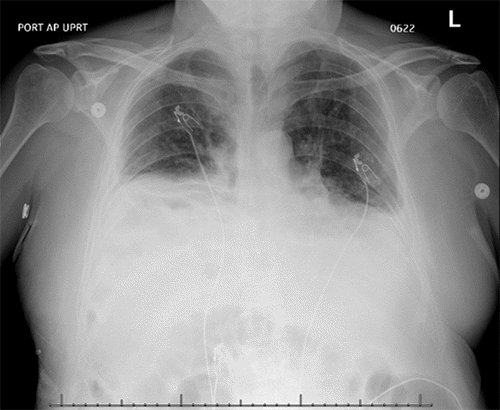

Figure 5. Immediate Postoperative Chest X-ray (POD 0). Published with Permission

Anteroposterior chest X-ray obtained on postoperative day 0, immediately following the initial diaphragmatic hernia repair

An immediate postoperative chest X-ray (CXR) demonstrated an appropriate position of the right hemidiaphragm (Figure 5). Serial bladder pressure measurements were monitored for potential abdominal compartment syndrome due to the LOD; on postoperative day (POD) 0, bladder pressure was 16 mmHg. The patient required reintubation on POD 1 due to concerns for delirium tremens. On POD 4, he was successfully extubated and placed on 15 L/min of oxygen via nasal cannula. Concurrently, his bladder pressure acutely decreased to 9 mmHg. A follow-up CXR obtained after extubation revealed a significant elevation of the right hemidiaphragm (Figure 6). This finding, coupled with the change in bladder pressure and concern for herniated bowel visible on CXR, prompted an urgent CT scan of the chest. The CT confirmed recurrence of a large right diaphragmatic hernia containing the liver, small bowel, and colon.